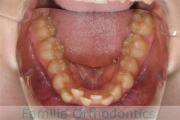

No.22V-449

- 主な症状:

- 上顎前突

- その他の症状:

- 叢生

- 年齢:

- 14歳

- 性別:

- 男性

- 抜歯部位

- 上:

- 44

- 下:

- 8448

- 主な使用装置:

- FEA

- 治療にかかった費用:

- 87万円

歯並びをきれいにしたいということで来院されました。上下左右から小臼歯を抜歯して、マルチブラケット法を行っています。2年弱、25回程度の通院が必要でした。

かなり強い叢生(でこぼこ、凹凸、ガタガタ)ですので、保定をしっかりしないと後戻りのリスクがあります。

- ≫治療前

-

上顎

下顎